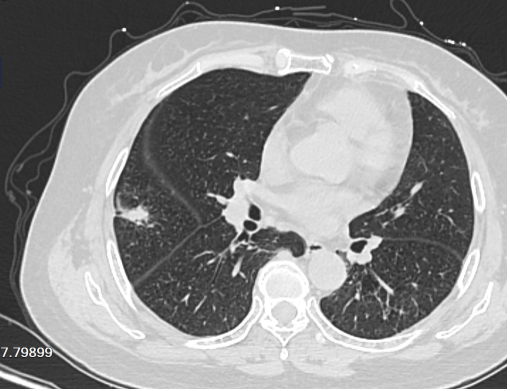

(三)AI智能小结节分析的应用:计算机可以通过自动分割和容积计算方法帮助放射科医生检测到非常小的结节。但AI也会有假阳性、假阴性结果出现,此时就需要放射科医生根据经验来判断AI智能结果是否准确。人脑与智能相结合,使得肺结节的检出更为准确。

图片53.png

图一 AI智能识别肺结节